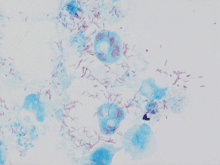

| Rickettsia conorii observed in Vero cells (red rods; magnification ×1,000)[1] | |

Rickettsia conorii is a Gram-negative, obligate intracellular bacterium of the genus Rickettsia that causes human disease called boutonneuse fever, Mediterranean spotted fever, Israeli tick typhus, Astrakhan spotted fever, Kenya tick typhus, Indian tick typhus, or other names that designate the locality of occurrence while having distinct clinical features.[3][4] It is a member of the spotted fever group and the most geographically dispersed species in the group, recognized in most of the regions bordering on the Mediterranean Sea and Black Sea, Israel, Kenya, and other parts of North, Central, and South Africa, and India.[3] The prevailing vector is the brown dog tick, Rhipicephalus sanguineus. The bacterium was isolated by Emile Brumpt in 1932[5] and named after A. Conor, who in collaboration with A. Bruch, provided the first description of boutonneuse fever in Tunisia in 1910.[6]